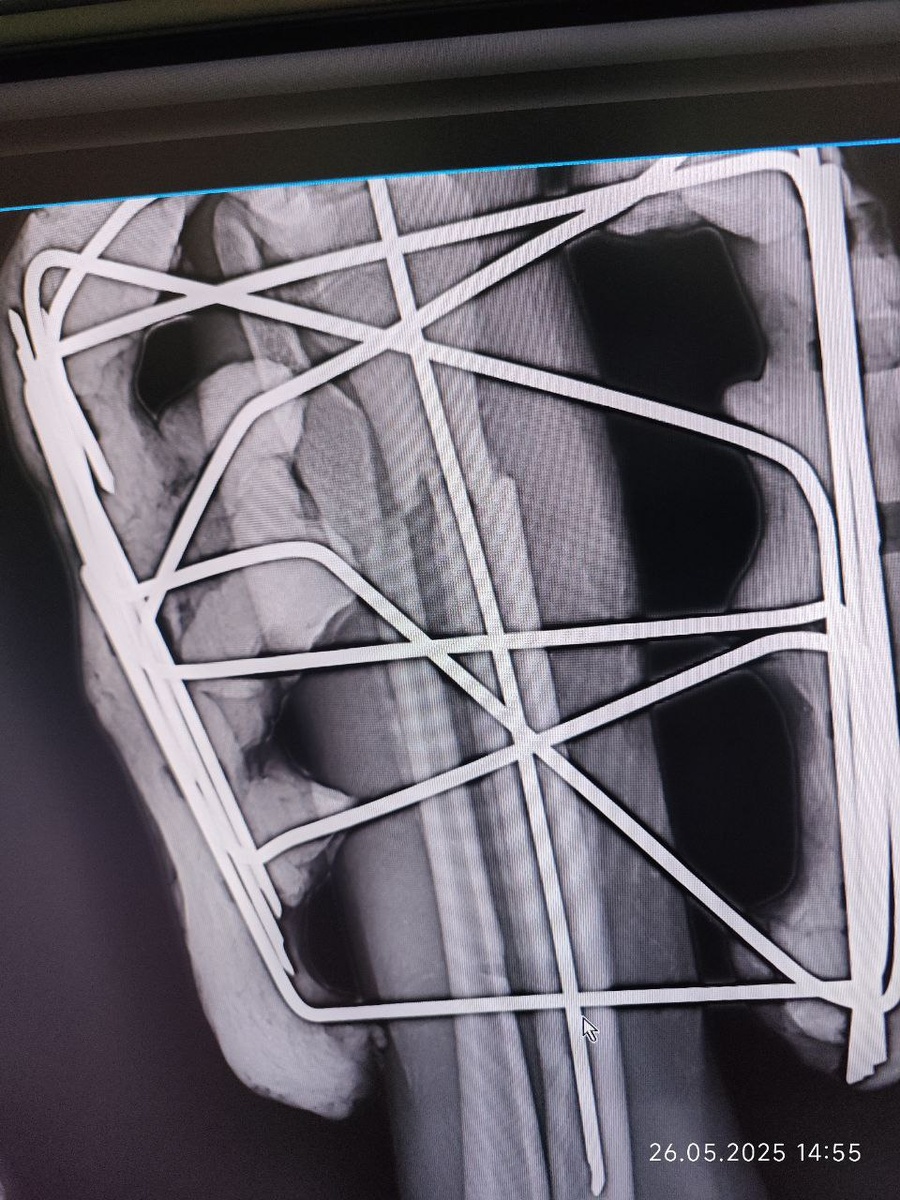

У Норда всё хорошо

У Норда всё хорошо 🥰 #шансожители

У Норда всё хорошо 🥰